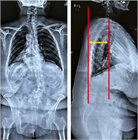

1. 矢状面バランス評価の指標を記載。

1. 若年者での脊柱変形は、先天性側弯症や思春期に発症する特発性側弯症が多く、通常痛みや機能障害を伴わない場合が多いが、成長に伴い変形が増悪する可能性が高いので見過ごしてはならない。特に特発性側弯症は、思春期の急速な成長期に進行するリスクが高いため、早期発見と適切な介入が重要である。